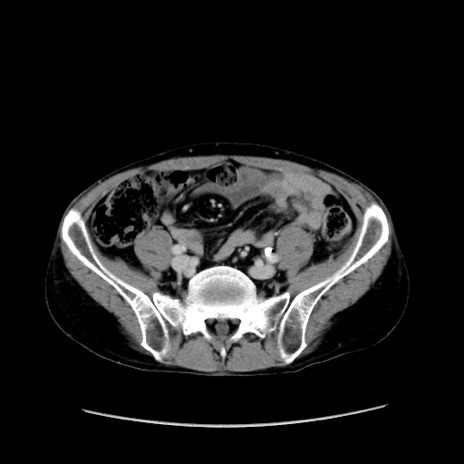

症例37(横断像)

【症例】40歳代 男性

【主訴】腹痛

【現病歴】4時間ほど前に電車に乗車中に臍部上より腹痛出現。徐々に増悪し起立困難となり、救急外来受診。生ものは数日食べていない。今朝お雑煮を食べた。

【身体所見】BT 36.8℃、BP 117/84mmHg、HR 91/min、SpO2 97%、苦悶様、腹部:臍上部広範囲圧痛あり、反跳痛±

【データ】WBC 8100、CRP 0.03